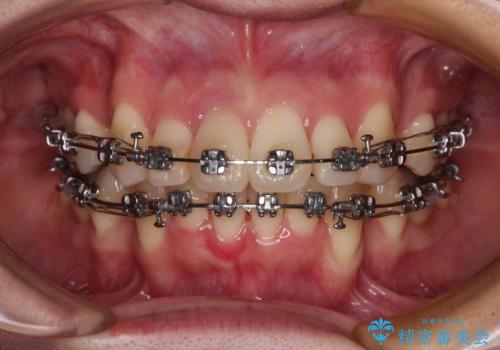

- メタルブラケット

- 八重歯と上の前歯が出っ歯になっていることを気にして来院された患者様です。

横から見た際の口元の飛び出した印象も改善したいとのことで、上下左右の第一小臼歯4本を抜歯し、ワイヤー装置にて抜歯矯正を行うこととしました。